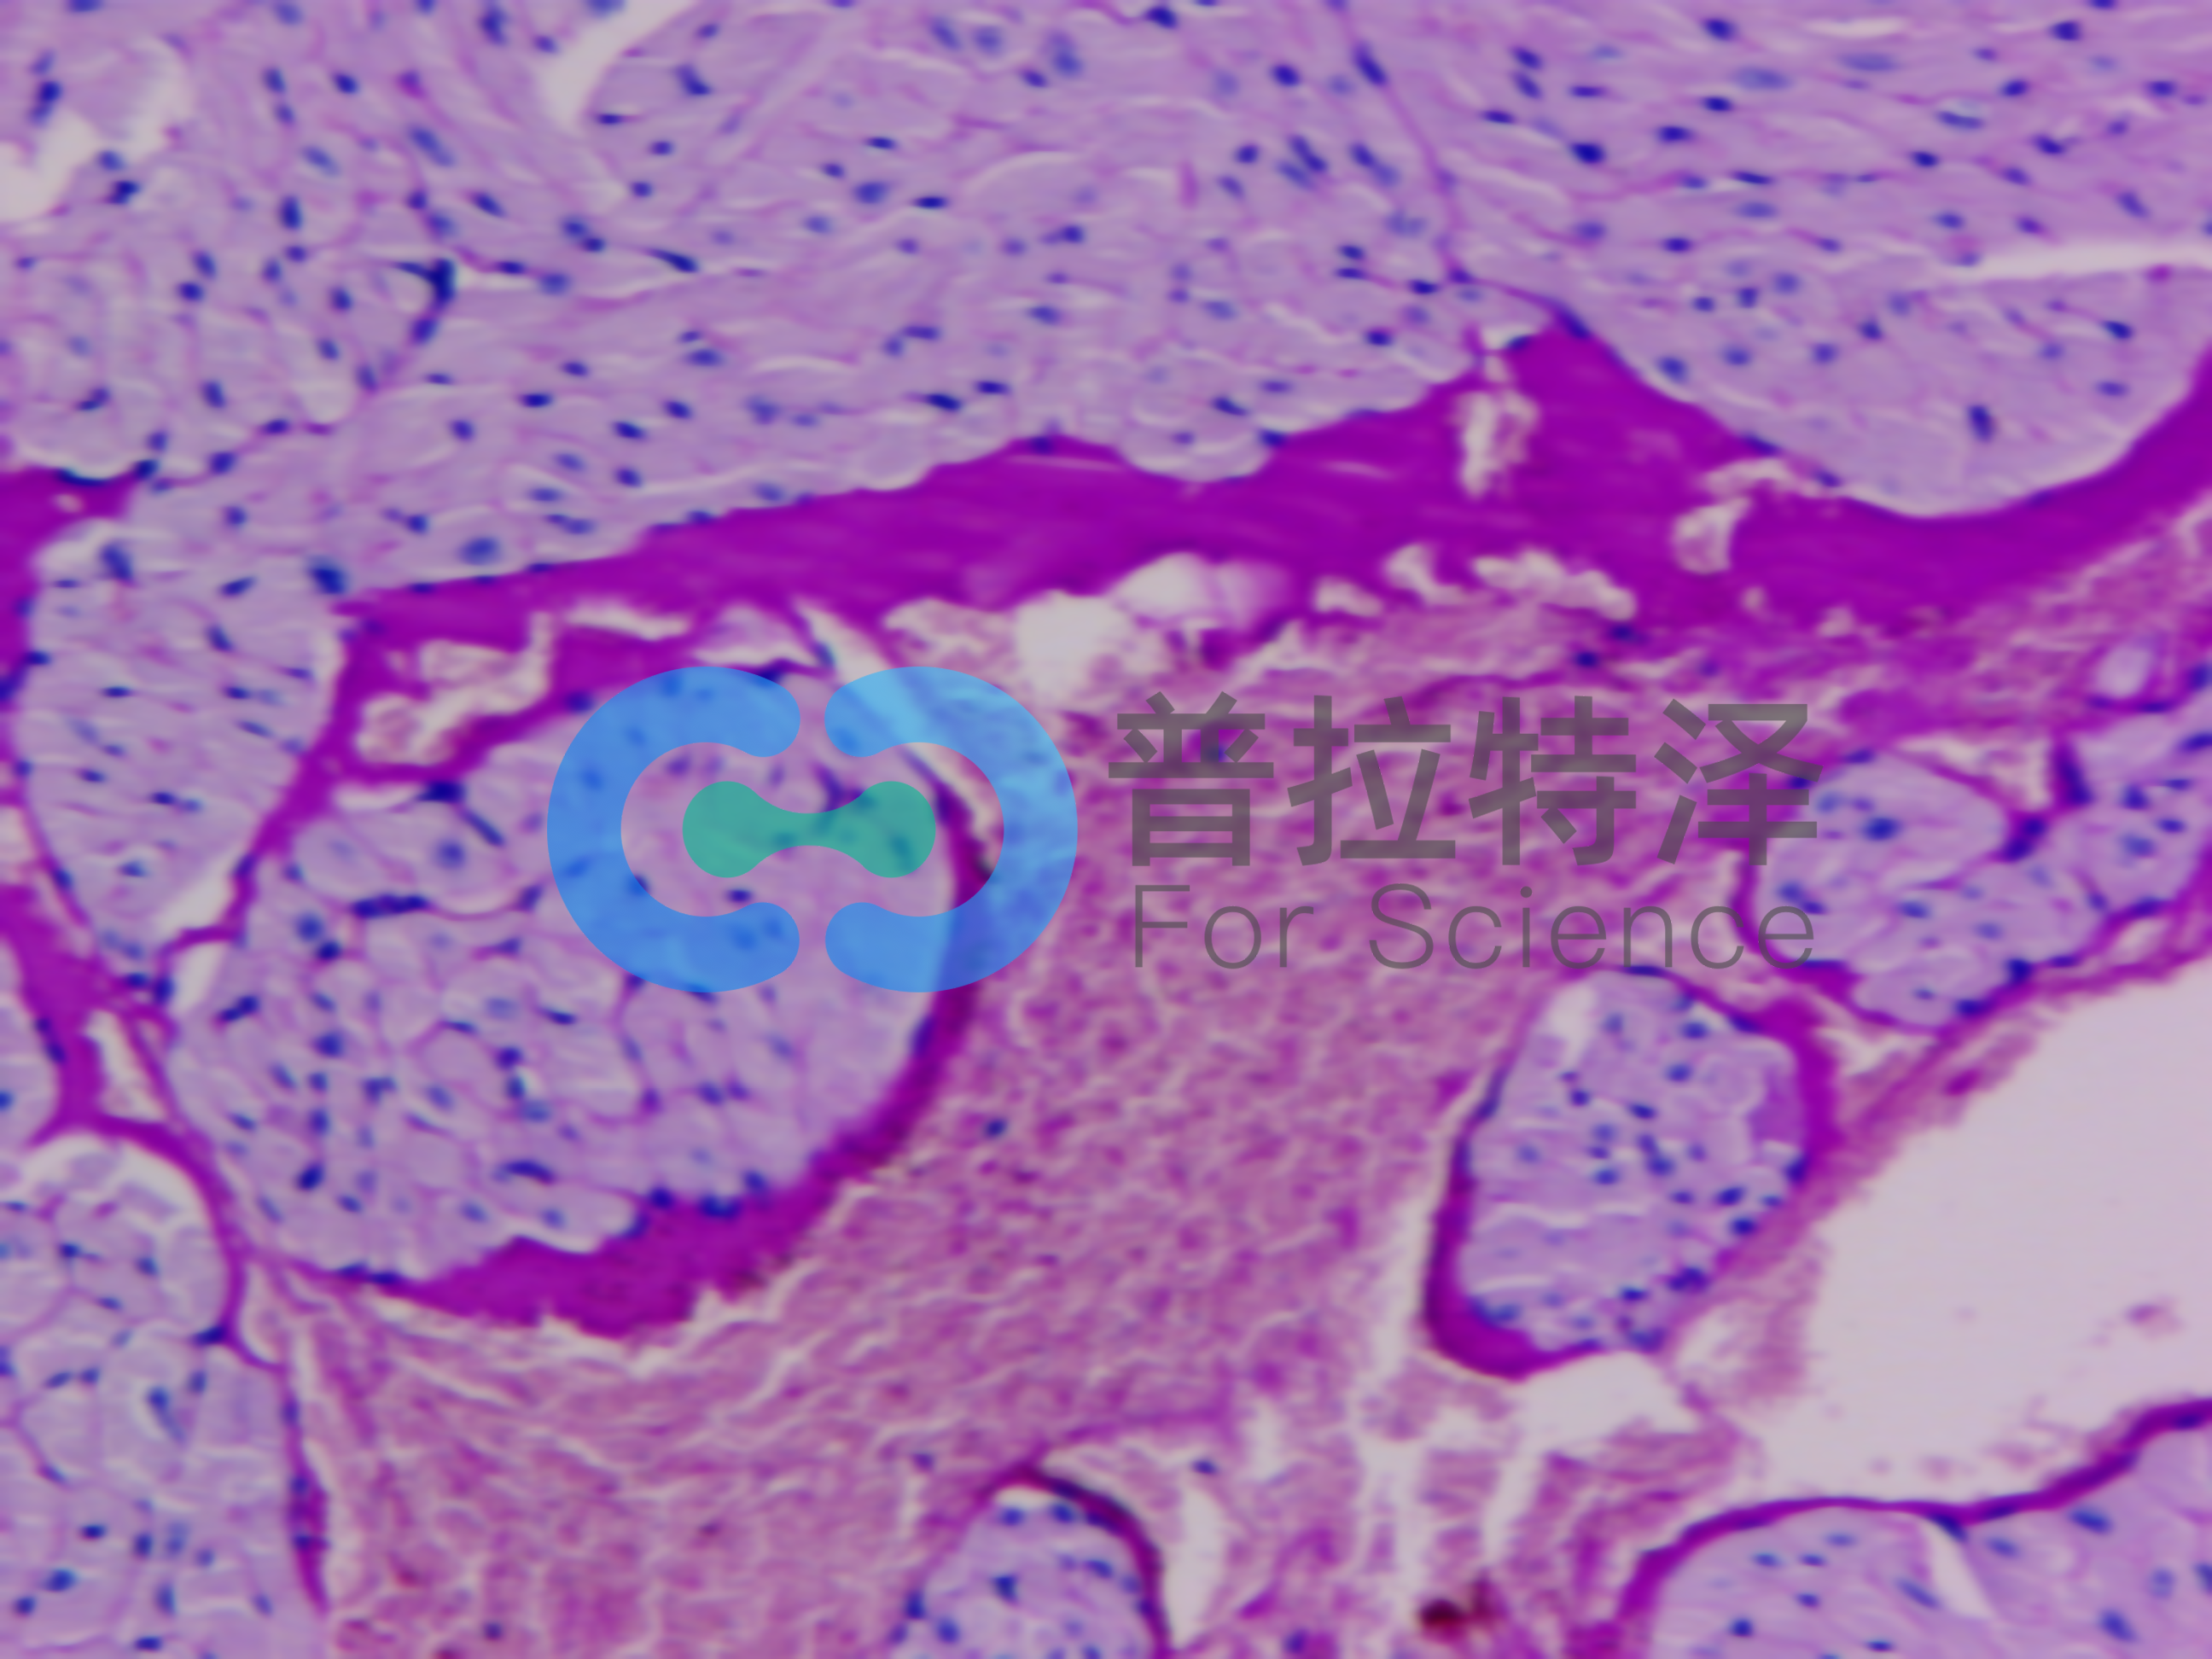

實(shí)驗(yàn)原理:糖原染色是病理學(xué)中常規(guī)的染色方法之一,氧化劑能氧化糖類(lèi)及有關(guān)物質(zhì)中的1,2-乙二醇基,使之變?yōu)槎┡cSchiff試劑能結(jié)合成一種品紅化合物,產(chǎn)生紫紅色。PAS技術(shù)常用來(lái)顯示糖原和其他多糖,該染色液不僅能夠顯示糖原,還能顯示中性黏液性物質(zhì)和某些酸性物質(zhì),以及軟骨、垂體、霉菌、真菌、色素、淀粉樣物質(zhì)、基底膜等。

隨著醫(yī)學(xué)實(shí)驗(yàn)技術(shù)的發(fā)展,近年來(lái),糖原染色應(yīng)用的范圍更加廣泛,如用以證明與鑒別細(xì)胞內(nèi)空泡狀的性質(zhì),心肌病變及其他心血管疾病的診斷,糖原累積病診斷和研究,糖尿病的診斷和研究,用于某些腫瘤的診斷等。除用于糖原的鑒定和黏液的顯示外,還可以觀察腎小球基底膜、結(jié)腸杯狀細(xì)胞中性黏液物質(zhì)、阿米巴滋養(yǎng)體和霉菌的著色。為臨床診斷、分類(lèi)和治療提供了重要的依據(jù)。